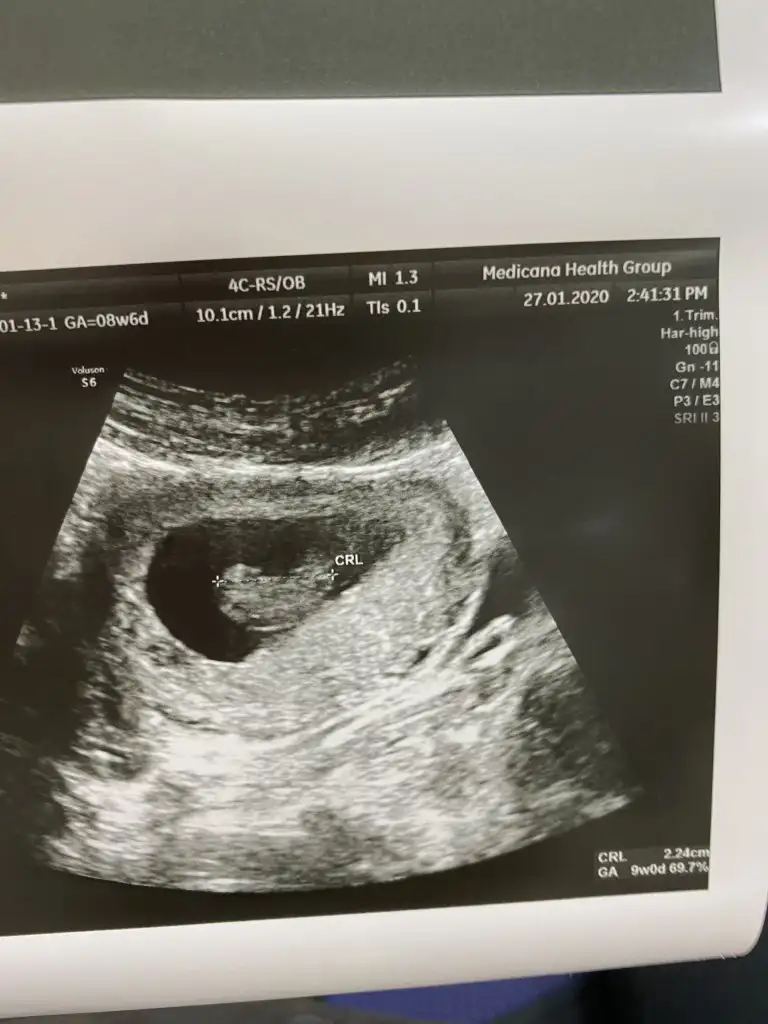

Dr + tam nuba denk getirmiş başka usg varmı12+4 banada yorumlarmisijizIkra meyra

Baska yokDr + tam nuba denk getirmiş başka usg varmı![]()

Dr + tam nuba denk getirmiş başka usg varmı![]()

Bu göre kız ama tutmayabilir tekrar usg olursa paylaşın .usteki 12+3 usg de kafa yapısı kız gibi ama nub göremiyorum .13+ usg olursa paylaşırsınızBaska yok![]()

Bu göre kız ama tutmayabilir tekrar usg olursa paylaşın .usteki 12+3 usg de kafa yapısı kız gibi ama nub göremiyorum .13+ usg olursa paylaşırsınız![]()